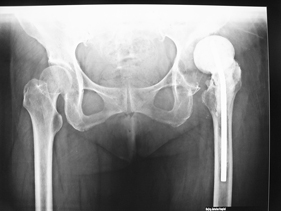

Department of Adult Joint Reconstructive Surgery

rivision total hip replacement for dislocation and severe bone defect

(pre-op) rivision total hip replacement for dislocation and severe bone defect

anterior-posterior view of bilateral hips